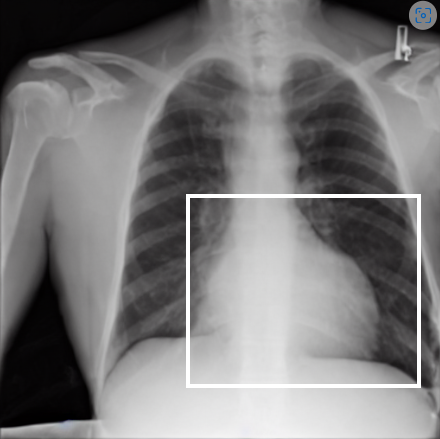

4.1 Qualitative Evaluation of Healthy Counterpart Generation

Example images from the disease COVID-19 Radiography Database and their generative healthy counterparts are given in figure 2. The images on the far left are instances of the lung opacity class from the real images in the dataset. The images in the middle column are examples of the generated healthy counterfactuals obtained via latent space diffusion, with RadBERT-guided textual-conditioning via a conditional prompt “normal chest x-ray”. A total of 75 diffusion inference steps are used with image conditioning strength=0.85 and guidance scale=7.5. (The former indicates the level of constraint on changes to the original input image and the latter is the weight given to the textual encoder conditioning in the generation of the image, ranging over [0,1] and [0,9], respectively).

Side-by-side inspection of the generated healthy counterfactuals (as per fig. 2) suggests that, as required, only minimal perturbation is made to the original image with respect to healthy pixels -i.e. localized image sites without structural medical defects. (In the top row, the medical structural defect in the original image is due to a lung opacity, and characterized via a relatively complex interaction between the imaging modality and subject manifesting as ‘gaps’ in the corresponding portions of the lung scan). The healthy/non-healthy discrepancy maps in all of these cases are obtained via masked subtraction of the original image from the generated image (the ground truth segmentation masks correspond to the broad area of interest –i.e. the complete lung). The generated healthy tissue is thus a subset of the mask and is shown in the final column of fig. 2 for the respective cases.

In the context of a VANT-GAN[20]-based approach, this highlighted material constitutes the diagnostic counterfactual visual attribution, i.e. the selection of material relevant to the diagnosis of the unhealthy condition. Healthy counterfactual generation was performed for the complete datasets in the three unhealthy classes, i.e Lung opacity, Viral Pneumonia and COVID, examples of which are given in fig. 3 for the three classes (all of the generated healthy counterfactuals from this experiment can be found on https://huggingface.co/ammaradeel/diffusionVA). Visual inspection indicates that the generated counterfactuals are, in general, visually plausible with minimal perturbation made to the unhealthy image overall. Moreover, the healthy counterpart generation does not appear to unnecessarily affect aspects of the images unrelated to the medical condition, the model selectively making changes to the unhealthy regions in a structurally plausible manner, e.g. generating missing portions of the lung without generating extraneous lung material where it would be expected to normally exist (e.g. in the abdominal cavity).